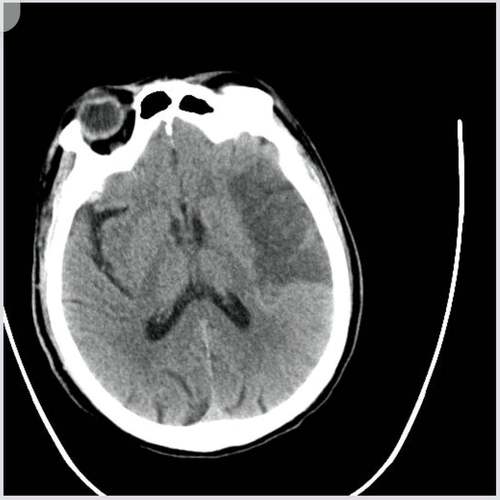

虽然超早期是最常见的原因,但少数情况下,以下类型的脑梗死在CT上也可能早期不显影或表现不典型:

- 小梗死灶:梗死范围非常小,位于脑的深部或非关键区域,CT上可能被周围的正常组织掩盖,无法显示。

- 脑干梗死:脑干(包括脑桥、中脑、延髓)的结构复杂且密度与周围组织相近,CT对其小的梗死灶不敏感。

- 出血性梗死:这是一种特殊的脑梗死,梗死区域继发出血,在早期,CT可能只看到缺血的低密度区,出血信号稍后才会出现。

- CT的局限性:CT对脑实质的分辨率不如MRI,对于一些微小的病变,CT确实存在盲区。